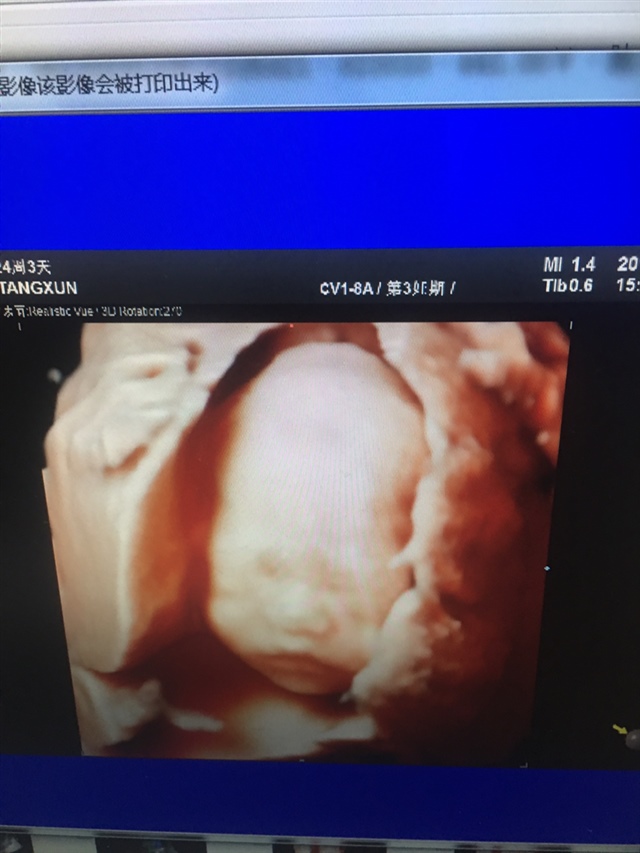

这是三维还是四维呀